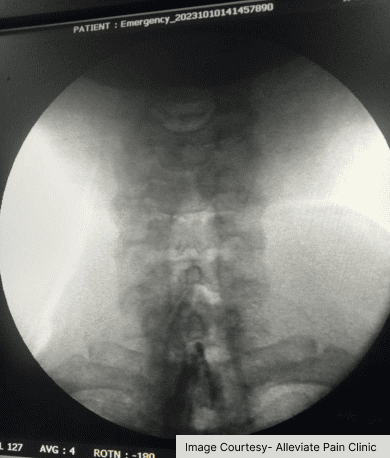

Group 14

Cervical epidural injection done under fluoroscopy at Alleviate Pain Clinic, Bengaluru

• What it does: Relieves muscle knots and spasms.

• Best for: Muscle strain, tension headaches.

Cervical Epidural Steroid Injections

• What it does: Relieves pain originating from inflamed cervical joints.